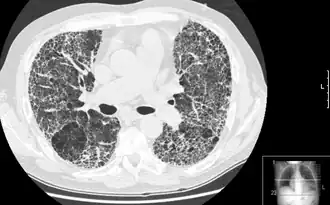

| КТВР, демонстрирующая признаки пневмофиброза |

Компьютерная томография высокого разрешения (КТВР) лёгких — медицинское исследование, применяемое для диагностики и оценки интерстициальных заболеваний лёгких. Метод использует специальные параметры КТ-сканирования, позволяющие оценить состояние лёгочной ткани и паренхима.